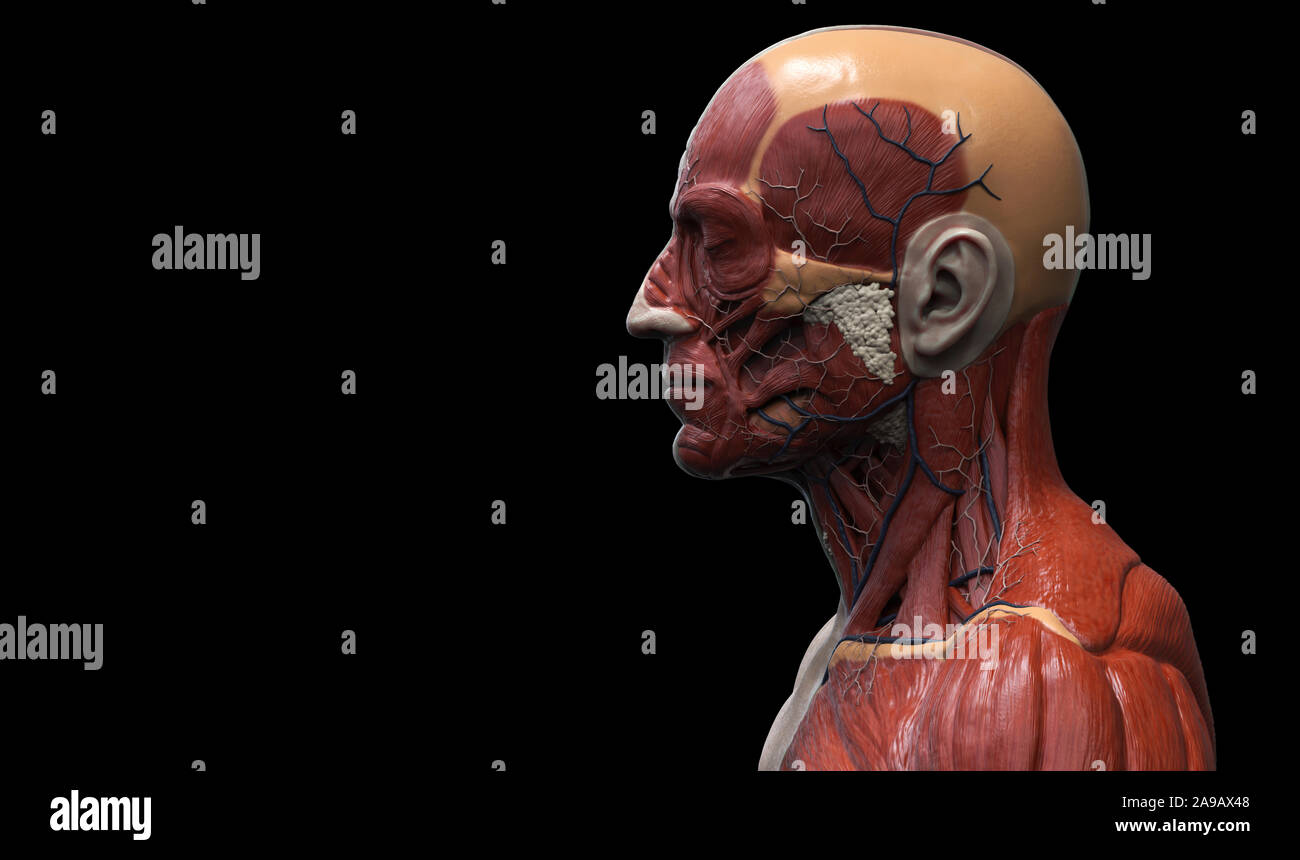

RF2A9AX48–Menschliche Körper Anatomie Muskeln Aufbau eines männlichen, Vorderansicht Seitenansicht und Perspektive, 3D-Rendering im Hintergrund